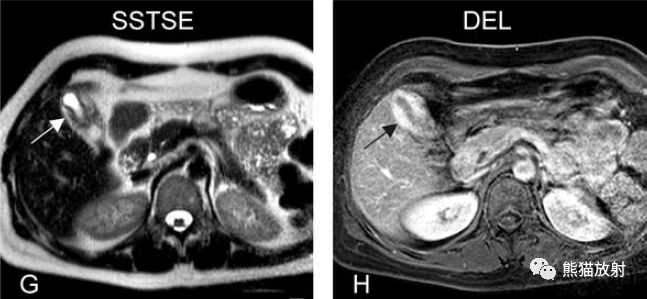

膽囊癌。病灶以膽囊為中心侵及肝臟,明顯彌散受限,由于病灶內含結締組織/纖維成分(T2低信號)導致肝被膜內陷,增強掃描動脈期明顯不均質強化,延遲期中心纖維成分延遲強化。表現類似肝內膽管細胞癌。

膽囊壁增厚(并肝硬化、門脈高壓、腹水)。T2WI顯示膽囊壁因水腫而光滑均勻增厚,增強延遲期顯示強化的膽囊壁(內外兩層:粘膜層和漿膜層),薄而清晰光滑。